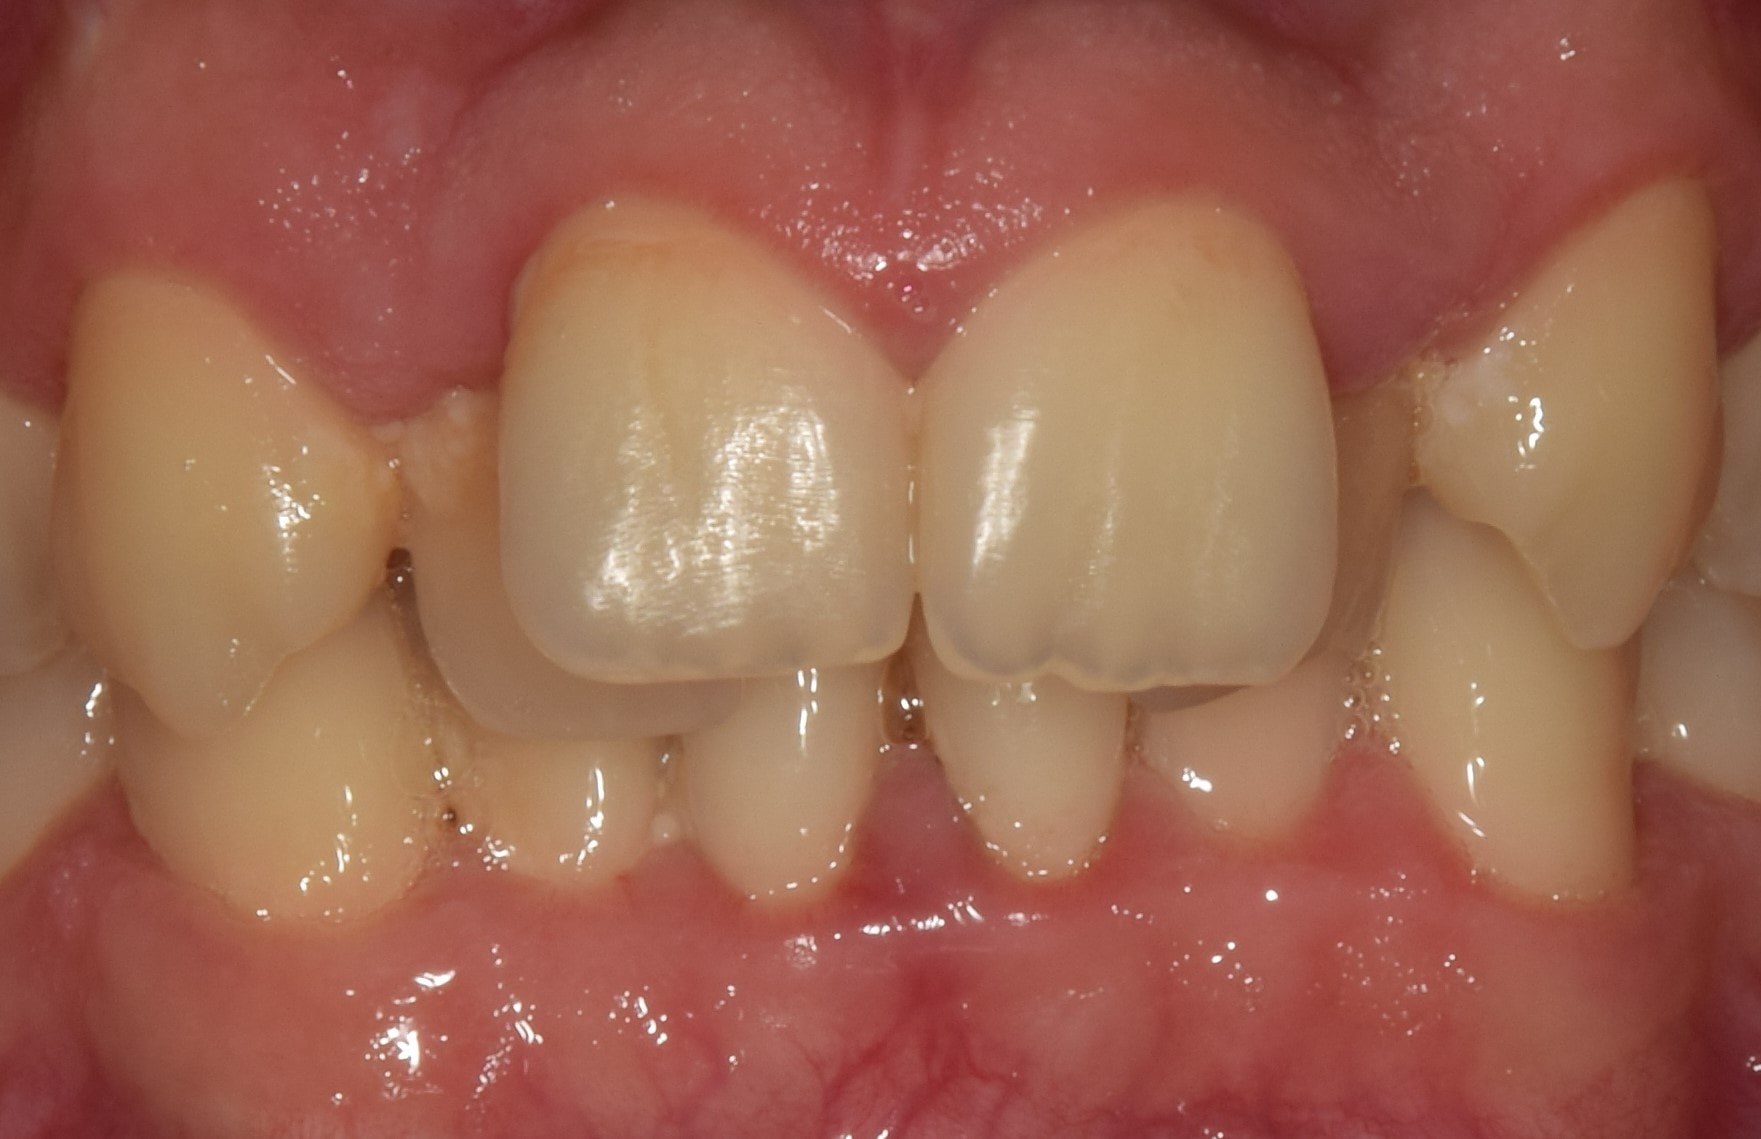

Diasthema medianum

Gyakori fogszabályozási probléma a két felső nagymetsző között jelentkező rés. Ellátását számos faktor befolyásolja. A vegyesfogazatban gyakori, legtöbbször normális jelenség, ami később spontán záródhat, ezért túlságosan korai ellátását semmi sem indokolja. Diasthemat eredményezhet például kifejezett ajakfék, számfeletti fog, kismetsző csírahiány.